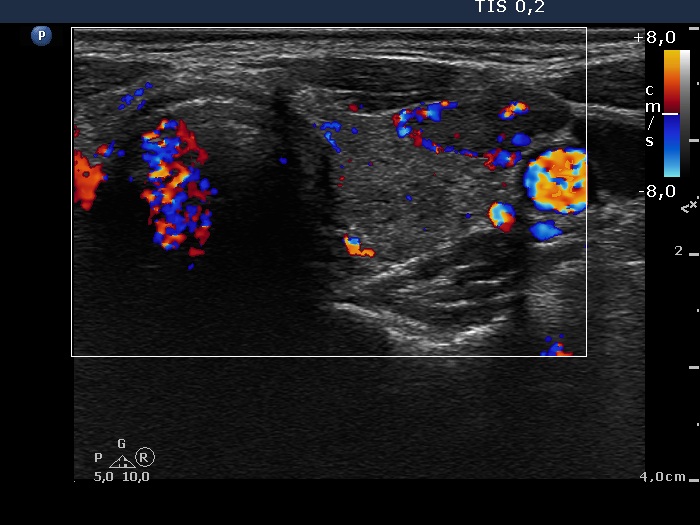

Discrete lesion or nodule in Hashimoto's thyroiditis - case 9 (644)

Thirteen months after the first examination (ultrasonographic picture 7)

Left lobe, transverse scan, color Doppler mode. The lesion presents signs of perinodular blood flow.